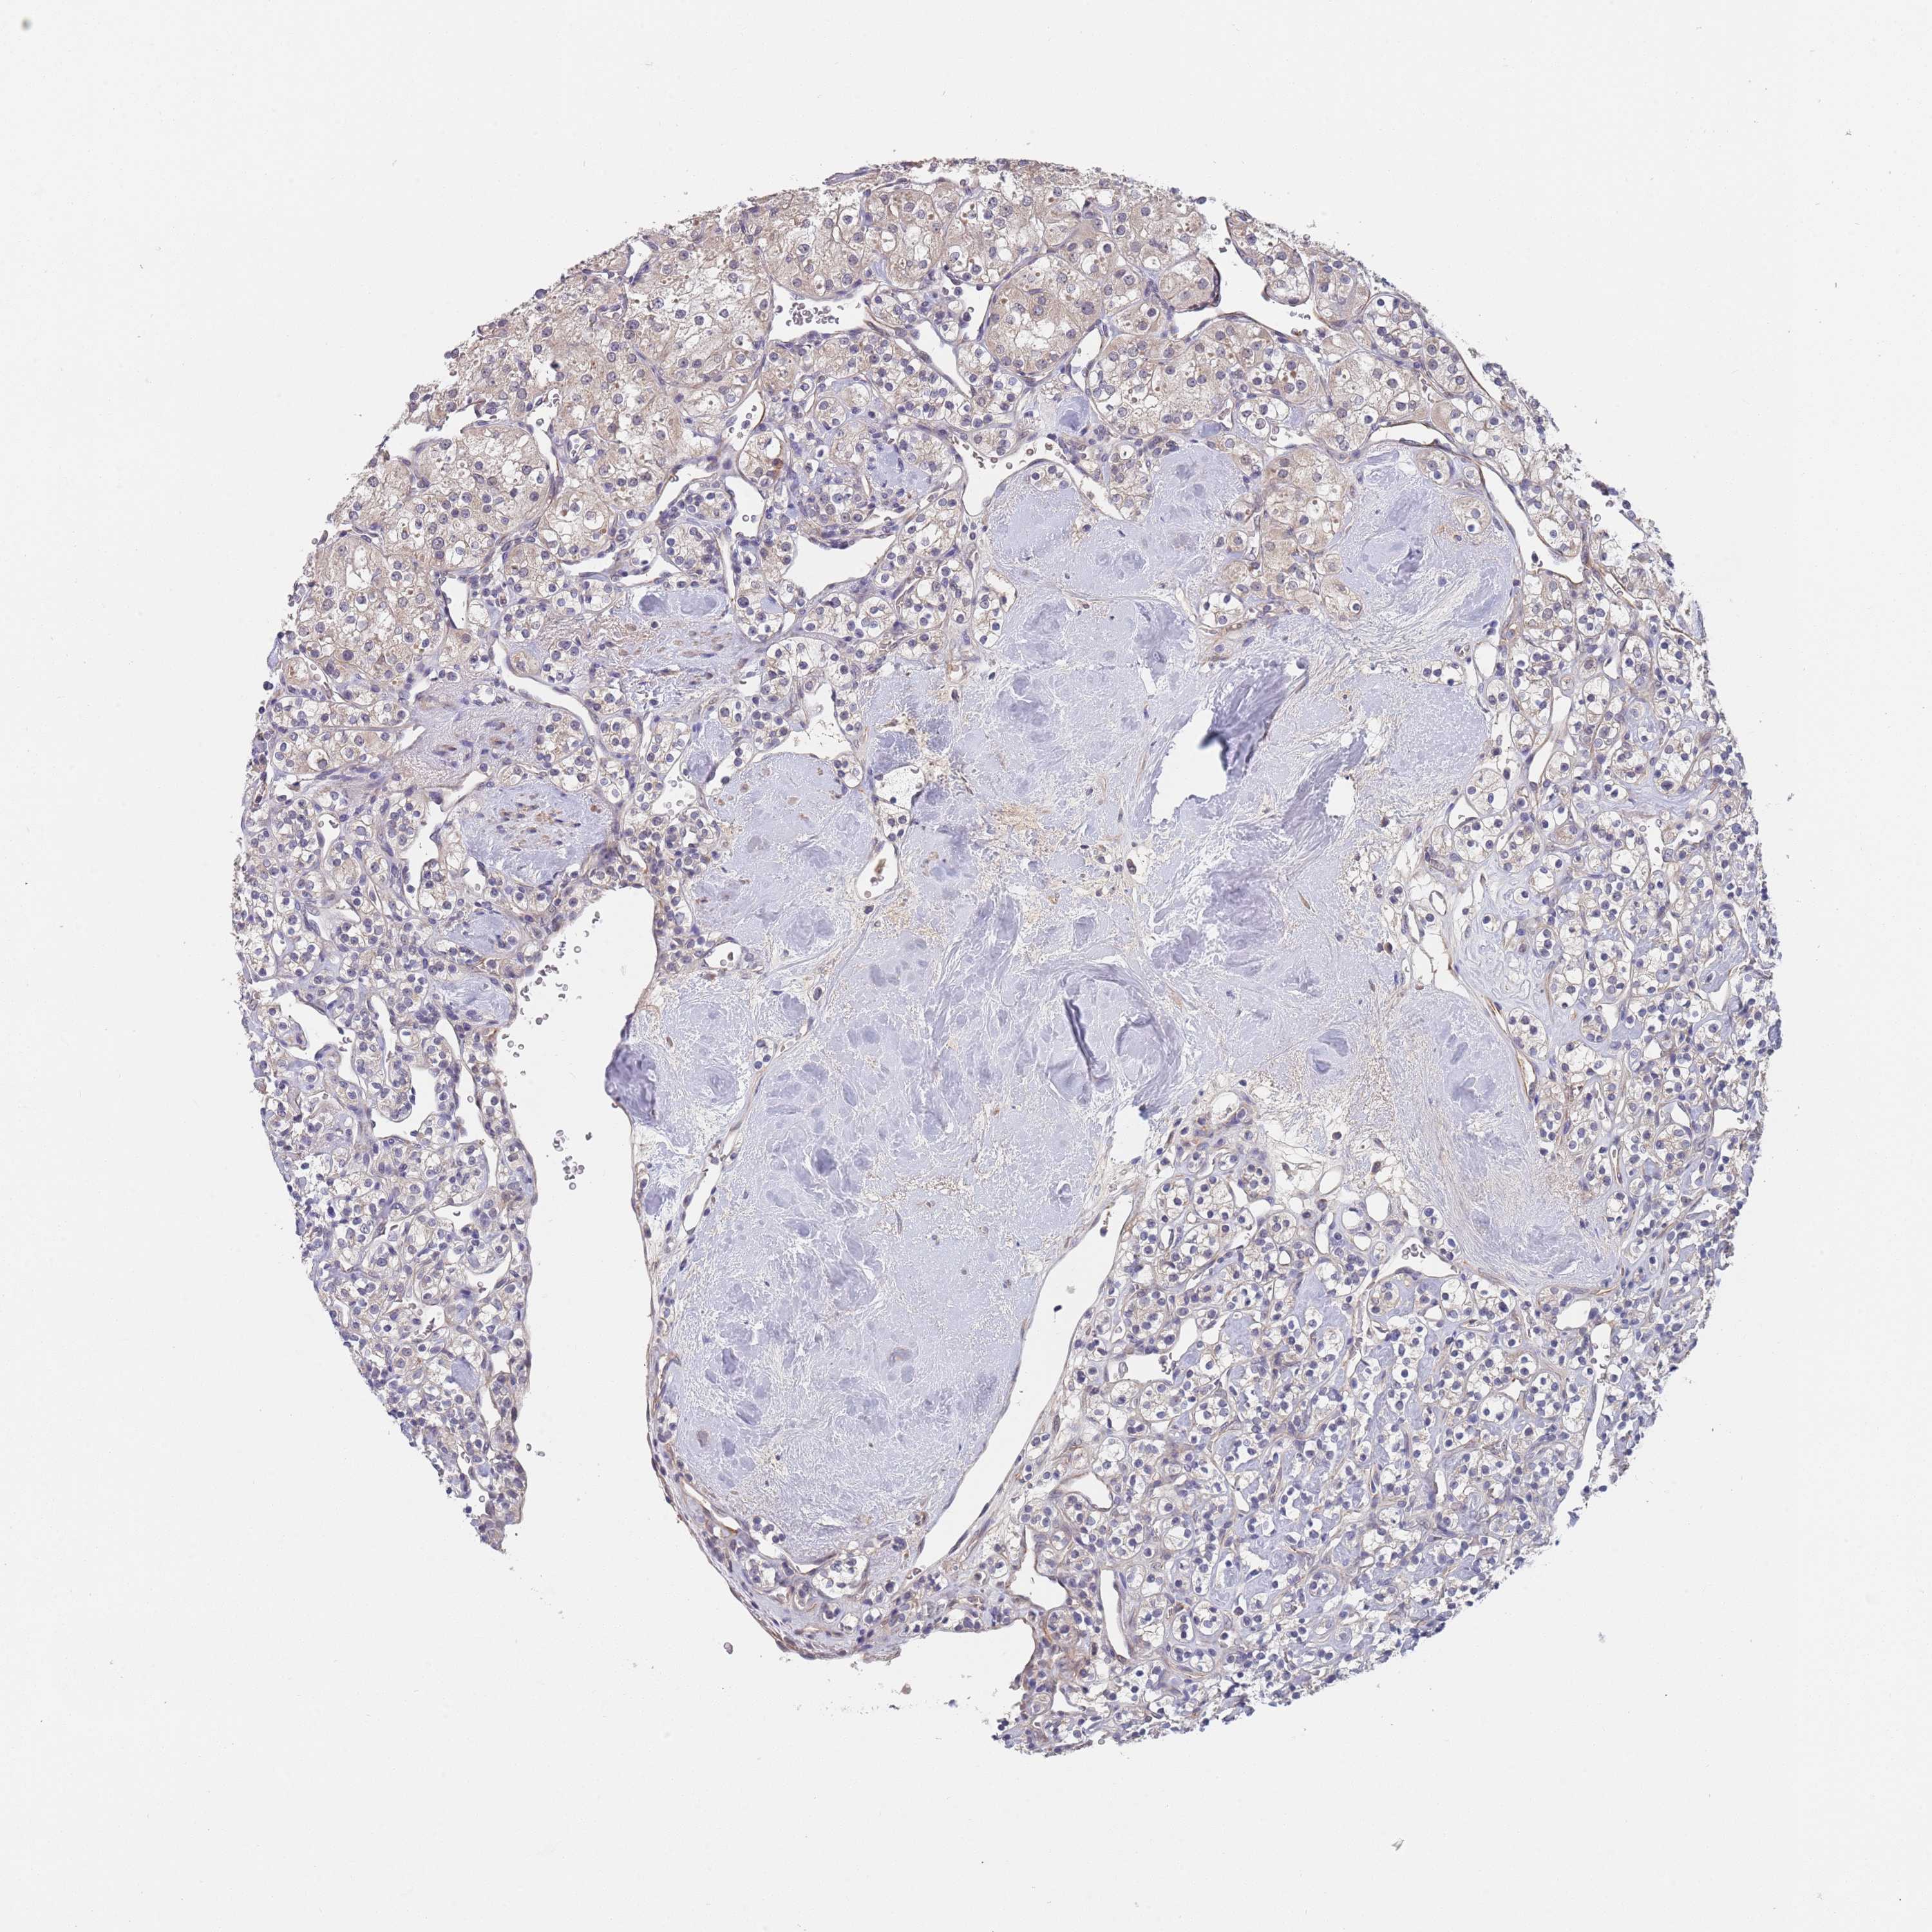

KIDNEY CHROMOPHOBE (TCGA) - Interactive survival scatter ploti

The Survival Scatter plot shows the clinical status (i.e. dead or alive) for all individuals in the patient cohort, based on the same data that underlies the corresponding Kaplan-Meier plots. Patients that are alive at last time for follow-up are shown in blue and patients who have died during the study are shown in red.

The x-axis shows the expression levels (FPKM) of the investigated gene in the tumor tissue at the time of diagnosis. The y-axis shows the follow-up time after diagnosis (years). Both axes are complimented with kernel density curves demonstrating the data density over the axes. The top density plot shows the expression levels (FPKM) distribution among dead (red) and alive patients (blue). The right density plot shows the data density of the survived years of dead patients with high and low expression levels respectively, stratified using the cutoff indicated by the vertical dashed line through the Survival Scatter plot. This cutoff is automatically defined based on the FPKM cutoff that minimizes the p-score. The cutoff can be changed by dragging the vertical line or by entering a cutoff value in the square labeled "Current cut-off".

Under the Survival Scatter plot the p-score landscape (black curve; left axis) is shown together with dead median separation (red curve; right axis). Dead median separation is the difference in median mRNA expression between patients who have died with high and low expression, respectively. It is calculated as follows: median FPKM expression of dead patients with high expression - median FPKM expression of dead patients with low expression. This is intended to aid the user in visually exploring custom cutoffs and the associated p-scores and dead median separation.

Individual patient data is displayed and can be filtered by clicking on one or more of the category buttons on the top of the page. Categories describing expression level and patient information include: high, low, alive, dead, female, male and tumor stages. The scale of the x-axis can be toggled between linear and log-scale by clicking on the "x log" button. Mouse-over function shows TCGA ID, patient information and mRNA expression (FPKM) for each patient.

& Survival analysisi

Kaplan-Meier plots summarize results from analysis of correlation between mRNA expression level and patient survival. Patients were divided based on level of expression into one of the two groups "low" (under cut off) or "high" (over cut off). X-axis shows time for survival (years) and y-axis shows the probability of survival, where 1.0 corresponds to 100 percent.

B4GALT4 is potential prognostic, high expression is unfavorable in Kidney Chromophobe (TCGA)

Best expression cut offi

Based on the FPKM value of each gene, patients were classified into two groups and association between prognosis (survival) and gene expression (FPKM) was examined. The best expression cut-off refers the FPKM value that yields maximal difference with regard to survival between the two groups at the lowest log-rank P-value. Best expression cut-off was selected based on survival analysis .

When clicking on this number, the vertical dashed line indicating cut-off, the interactive survival plot, and the Kaplan-Meier curve will be adjusted to show results based on the best expression cut-off.

: 10.25

Median expressioni

Median expression refers to the median FPKM value calculated based on the gene expression (FPKM) data from all patients in this dataset. When clicking on this number, the vertical dashed line indicating cut-off, the interactive survival plot, and the Kaplan-Meier curve will be adjusted to show results based on the median expression.

: N/A

Median follow up timei

Median follow up time refers to the median time (years) after diagnosis with this type of cancer, based on clinical data from all patients in this dataset.

P scorei

Log-rank P value for Kaplan-Meier plot showing results from analysis of correlation between mRNA expression level and patient survival.

N/A

5-year survival highi

5-year survival for patients with higher expression than the expression cutoff.

For melanoma and glioma, 3-year survival is shown.

5-year survival lowi

5-year survival for patients with lower expression than the expression cutoff.

TCGA RNA samplesi

RNA-seq data is reported as average FPKM (number Fragments Per Kilobase of exon per Million reads), generated by the The Cancer Genome Atlas (TCGA) .

Normal distribution across the dataset is visualized with box plots, shown as median and 25th and 75th percentiles. Points are displayed as outliers if they are above or below 1.5 times the interquartile range. FPKM values of the individual samples are presented next to the box plot.

Average pTPM 12.2

Number of samples 64